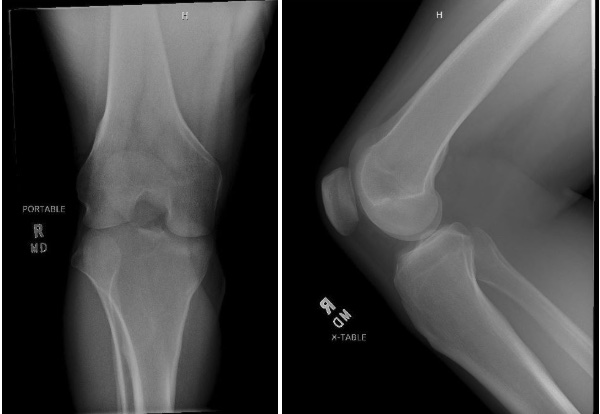

A 31-year-old male who presented to the emergency department for evaluation of right knee pain and inability to extend his knee with similar episodes prior. He was in a squatted position when he felt a snap and felt the knee lock with the inability to extend back to neutral. X-Rays were normal, but he remained unstable to extend despite medication

Initial Imaging

ED Treatment